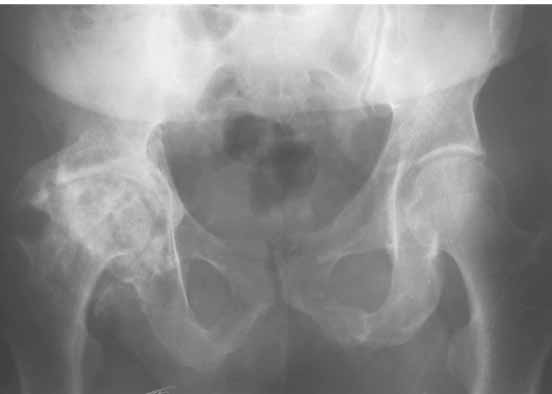

Для ответа на Ваши вопросы нужна, как минимум, обзорная

рентгенограмма таза в прямой проекции - многое станет ясно без слов.

Первые впечатления:

1. Вертикальное положение чашки;

2. Нарушение угла антеверсии ножки (судя по изображению малого вертела

на послеопреационной рентгенограмме).

3. Комбинация этих двух причин.

4. Видимо, тенденция к вывиху была уже на столе - вот Вам и кокситная повязка с надеждой на фиксацию протеза рубцом.

Обзорная рентгенограмма таза просто необходима. Удивительно, почему она не сделана сразу же после установки протеза.

После ее получения можно будет продемонстрировать причины проблемы.

ошибочно заданным углом антеверсии и, скорее всего, с избыточным удлинением - именно это мы и увидим на передне-задней рентгенограмме(!) таза.

1. AP X ray of the Pelvis is a must. It will likely show that right hip/ femur is longer than left. Even based on Rt Hip AP X Ray it is my impression.